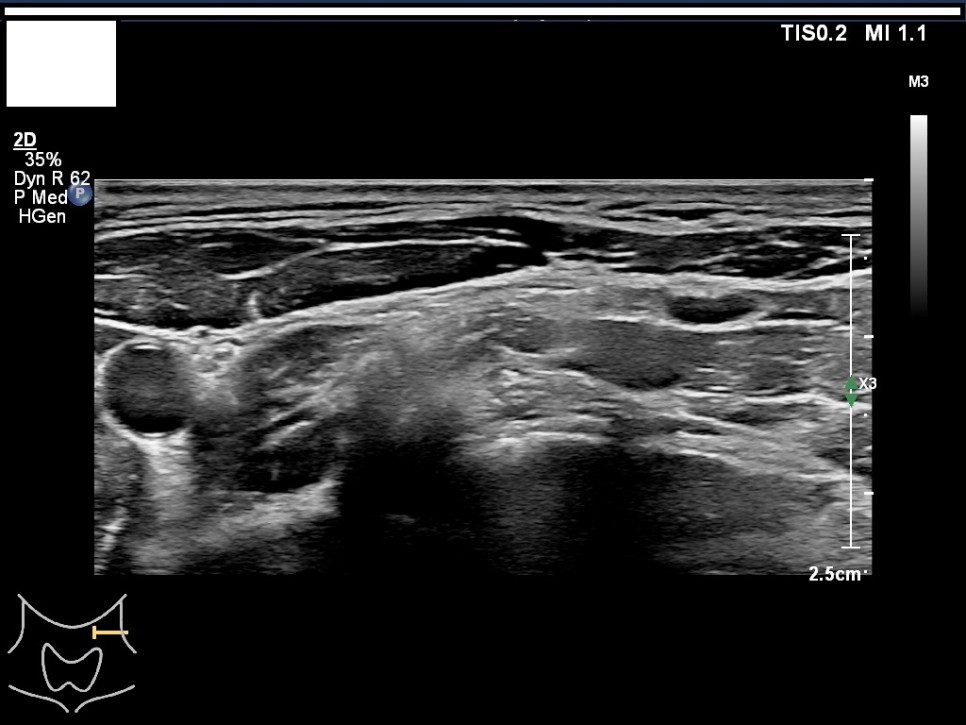

갑상선, 부갑상선 초음파 검사 급여 기준 1. 표준 영상의 범위 모든 영상에는 경부의 해부학적 위치(모식도나 문자)를 표기하여야 한다.

A) 병변이 없는 경우: 우엽 중부 가로 스캔, 우엽 중앙부 세로 스캔, 협부 가로 스캔, 좌엽 중부 가로 스캔, 좌엽 중앙부 세로 스캔, 우경부 림프절, 좌경부 림프절 나) 병변이 있는 경우: 병변이 없는 경우의 표준 영상과 함께 병변 부위에서 2개의 수직 관계 단면 영상(횡단/종단) 및 병변의 크기가 측정된 경우: 병변이 없는 경우의 표준 영상

Color Doppler / 우측 경부 림프절 Level1-4 / 우측 경부 림프절 level5

좌우 이하 선 악하선 가로 스캔 1, 2 / 좌경부 림프절 level 1-4

좌경부 림프절 5/우엽 중부 가로 스캔/우엽 중앙부 세로 스캔

우경부림프절/좌엽중앙세로 스캔/좌엽중앙가로스캔

좌측 경부 림프절 / 중심 경부 림프절 / 협부 옆 스캔 2. 판독 소견서가) 등록 번호, 성명, 생년월일 또는 연령, 성별, 검사명, 검사 일시, 판독 일시, 검사와 판독한 의사(면허 번호), 의료기관명, 검사 소견 및 결론 나) 검사 소견에는 갑상선 에코, 병변의 유무를 기술하여야 한다. 결절이 있을 경우 위치, 최대지름, 주요 소견, K-TIRADS의 내용을 기술하여야 하며, 암으로 진단된 결절을 추적할 경우 위치, 3방향 직경, 주요 소견, 전 검사와 변화 여부, 경부 림프절의 평가 및 이상 소견 여부를 기술하여야 하며, 경부 림프절에 이상이 있을 경우 위치, 크기, 주요 소견을 기술하여야 한다. 결절이 여러 개 있을 경우 암 위험도에 따라 선택적으로 기술할 수 있다. 또 소아 등에서의 환자의 협력도 음창 등이 좋지 않아 표준 영상 획득에 제한이 있는 경우 추가 기술해야 한다.